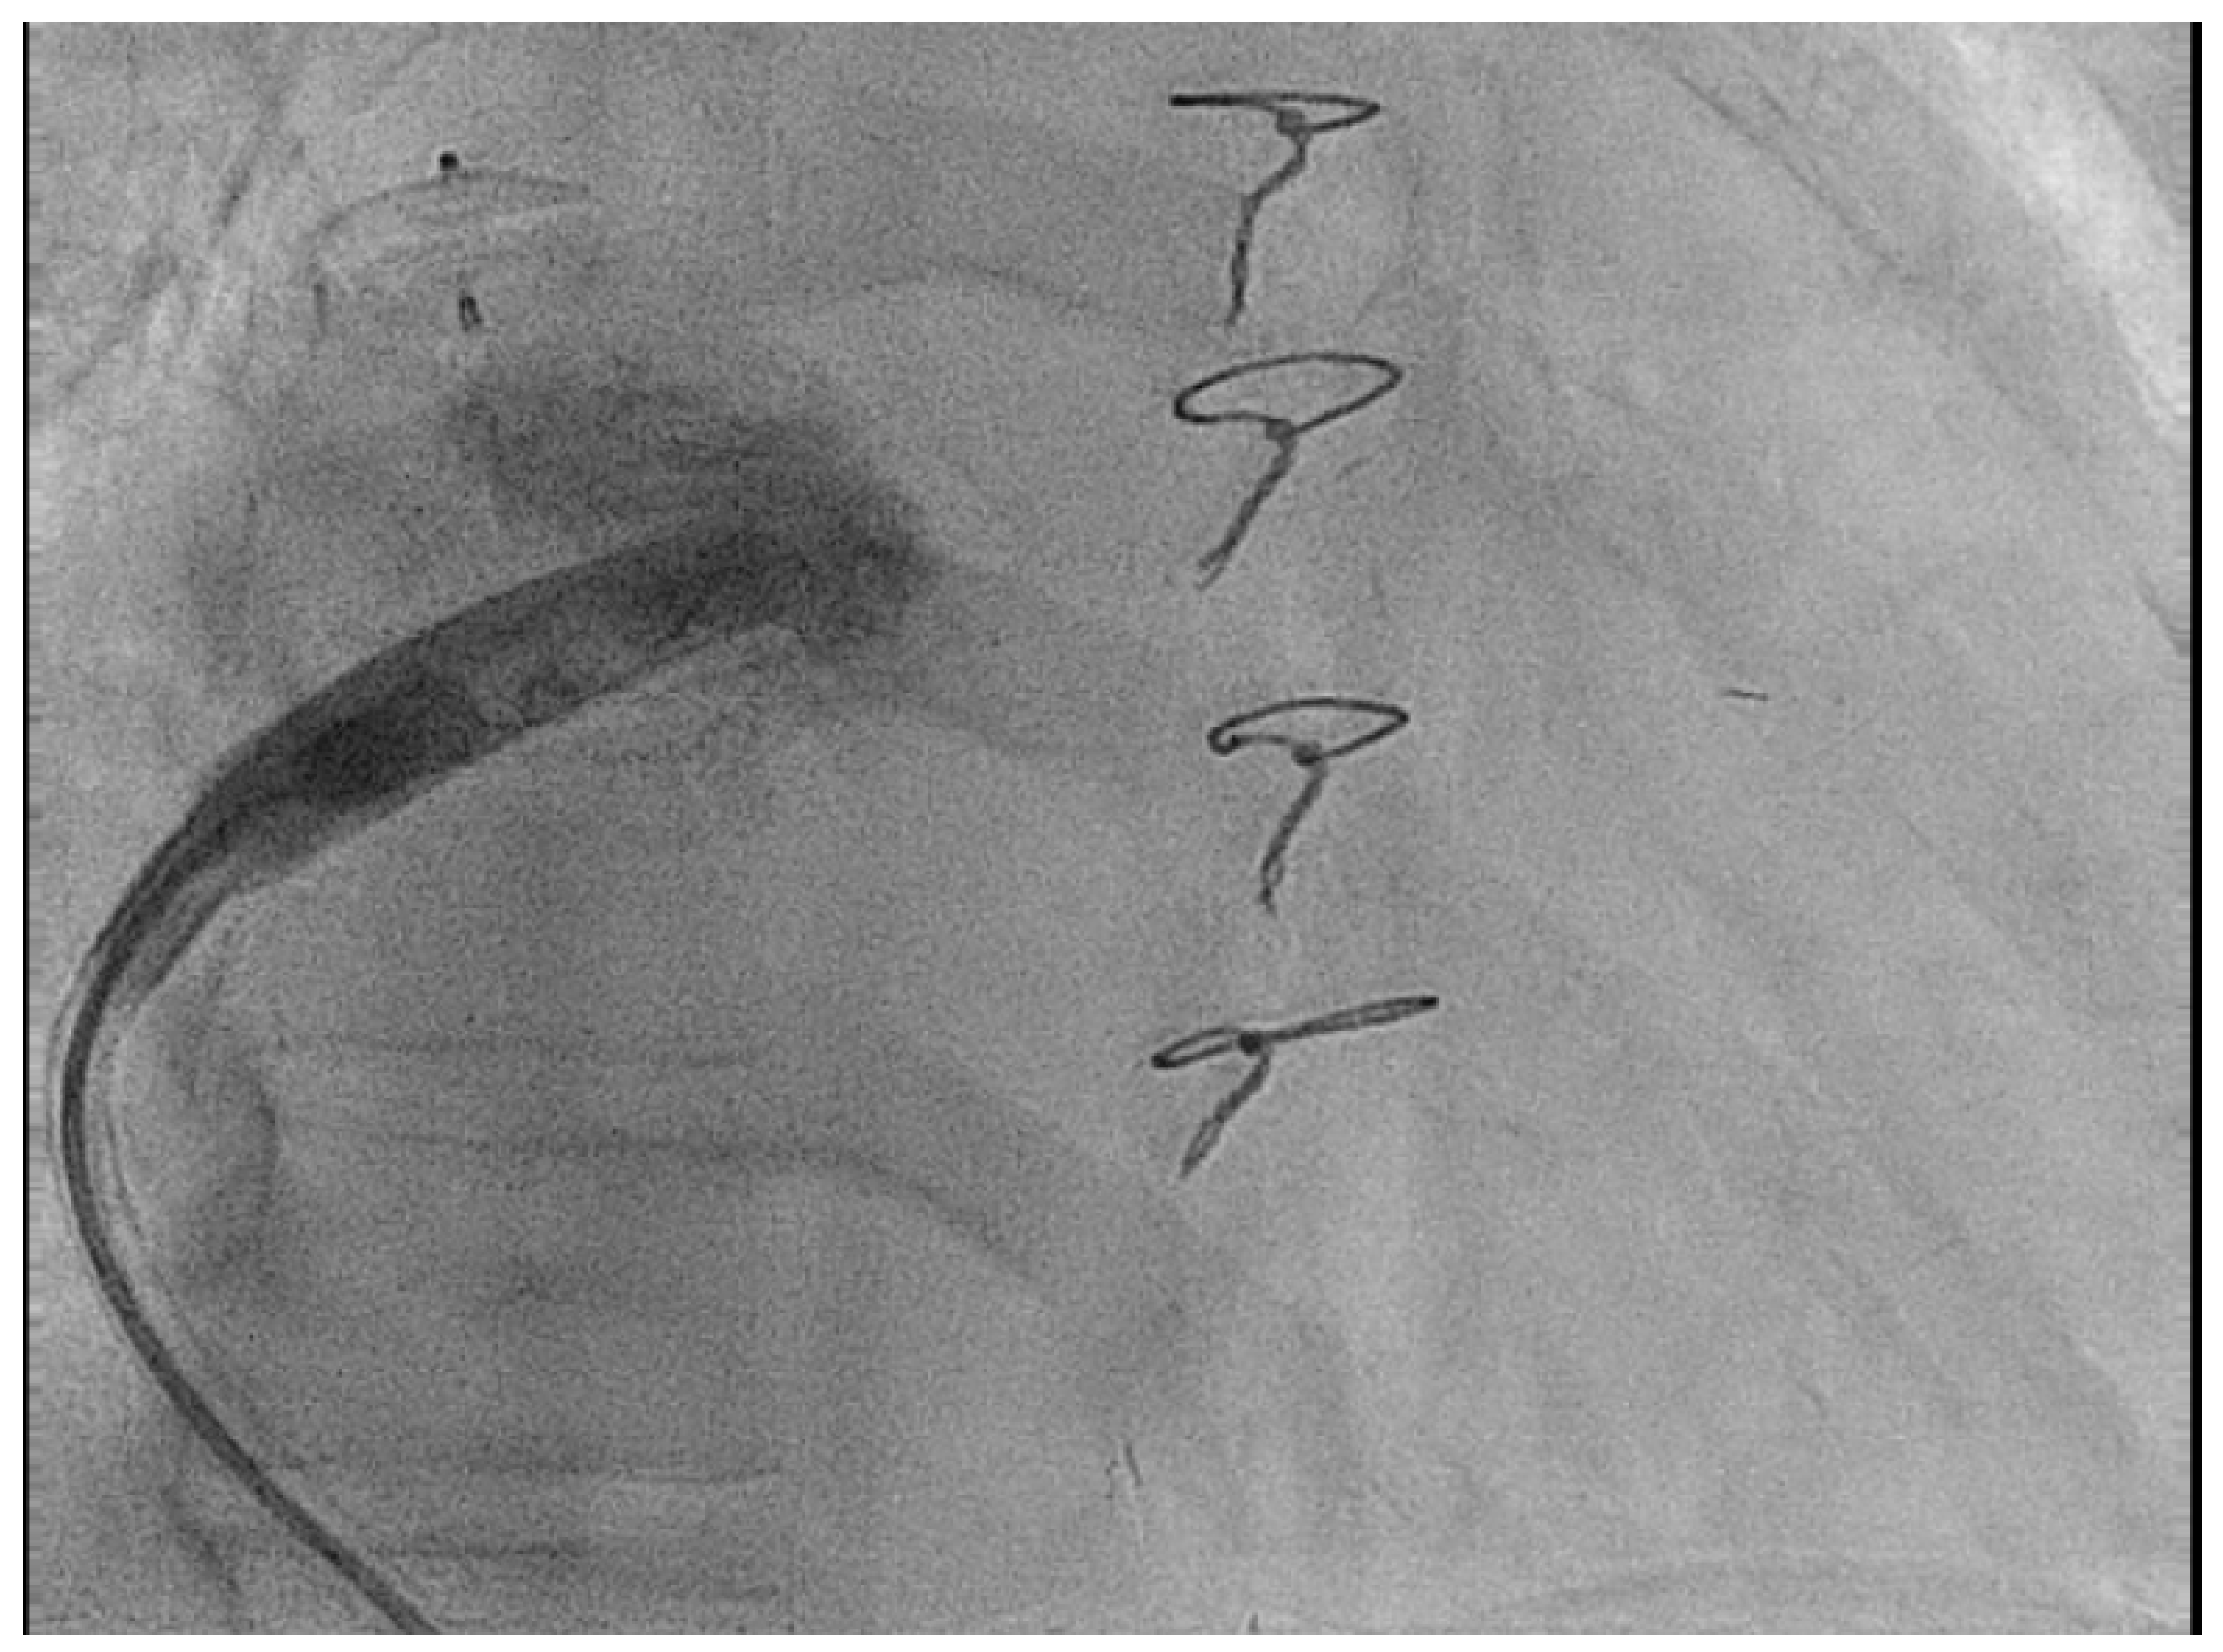

- Hayle, P.; Altayeb, F.; Hale, A.; Rao, A.; Ashrafi, R. Case report demonstrating novel approaches for leadless pacemaker implantation in the single ventricle heart. Eur. Heart J. Case Rep. 2025, 9, ytaf146. [Google Scholar] [CrossRef]

- Goulden, C.J.; Khanra, D.; Llewellyn, J.; Rao, A.; Evans, A.; Ashrafi, R. Novel approaches for leadless pacemaker implantation in the extra-cardiac Fontan cohort: Options to avoid leaded systems or epicardial pacing. J. Cardiovasc. Electrophysiol. 2023, 34, 2386–2392. [Google Scholar] [CrossRef]